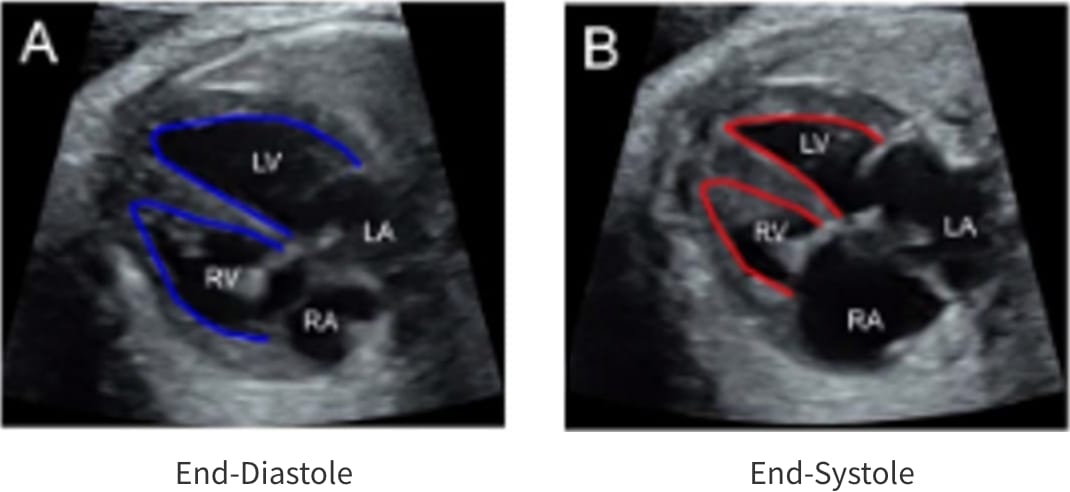

Fetal HQ

Fetal HQ®はSpeckle-Tracking法を用いて胎児心室壁の運動を解析する方法です。Speckle-Tracking法とは心筋の断層エコー画像上の小斑点(speckle)を追跡し心筋局所の機能を解析する方法で、成人の心臓超音波検査でも用いられています。一回数秒の動画の保存で複数の心機能が同時に評価できる新しい検査法です。

Fractional shortning

(拡張末期径−収縮末期径)/拡張末期径×100で表され、短軸で収縮能を評価する。SegmentごとにFSを算出できる。

Fractional area change

(拡張末期面積–収縮末期面積)/拡張末期面積×100で表され、面積で収縮能を評価する。

Fetal HQの臨床における活用はまだ限定的です。当院では先天性心疾患の胎児や、双胎間輸血症候群・胎児胸水・胎児貧血といった胎児治療が必要な胎児の心機能を評価するために、従来用いられている心機能の評価項目に加え、Fetal HQを用いて心エコー検査を行っています。データを積み上げ、Fetal HQの活用の幅を広げていきます。

胎児心不全の一例:著明な心拡大と収縮機能低下を認める